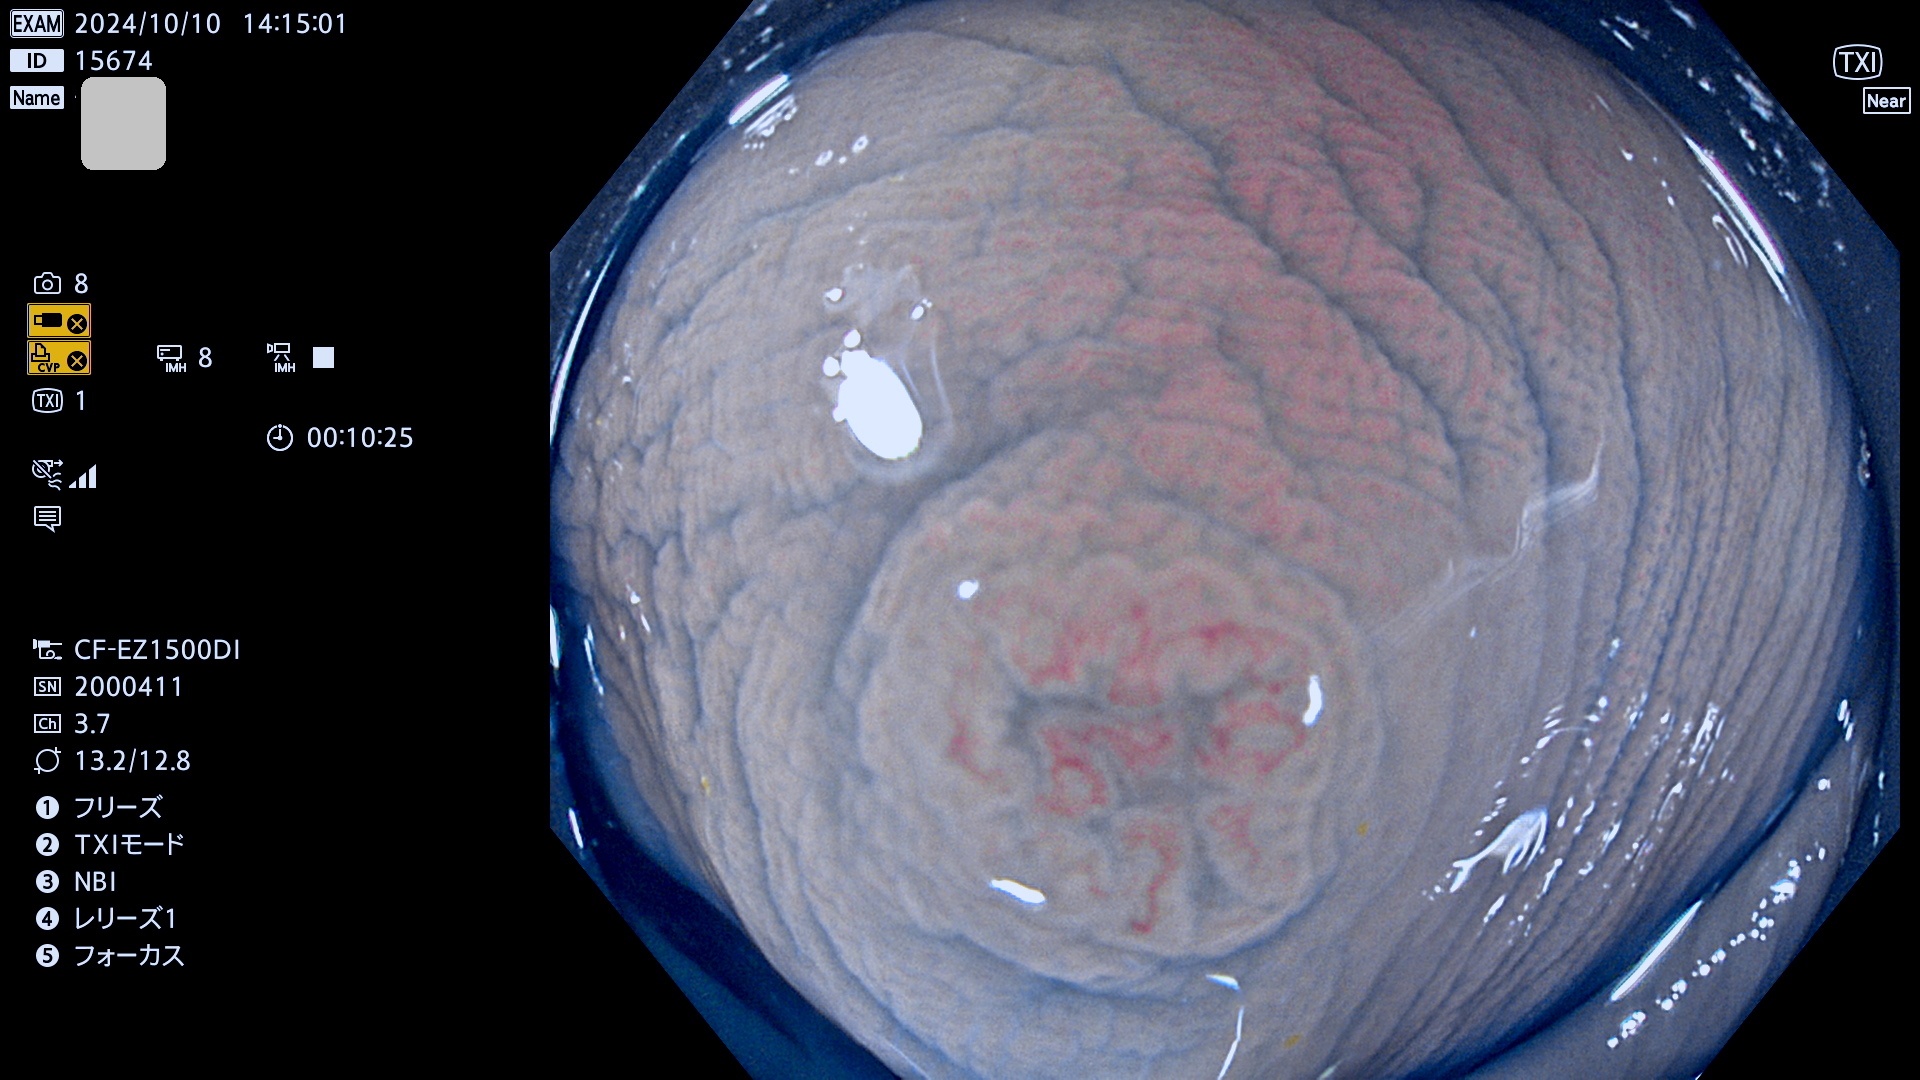

完全に平坦な物をUb、陥凹している物をUcと呼びます。最も発見が難しく危険な病変です。

抽出の対象期間 2024年10月10日〜10月13日の4日間(48件の検査)7件 (7/48=14%)